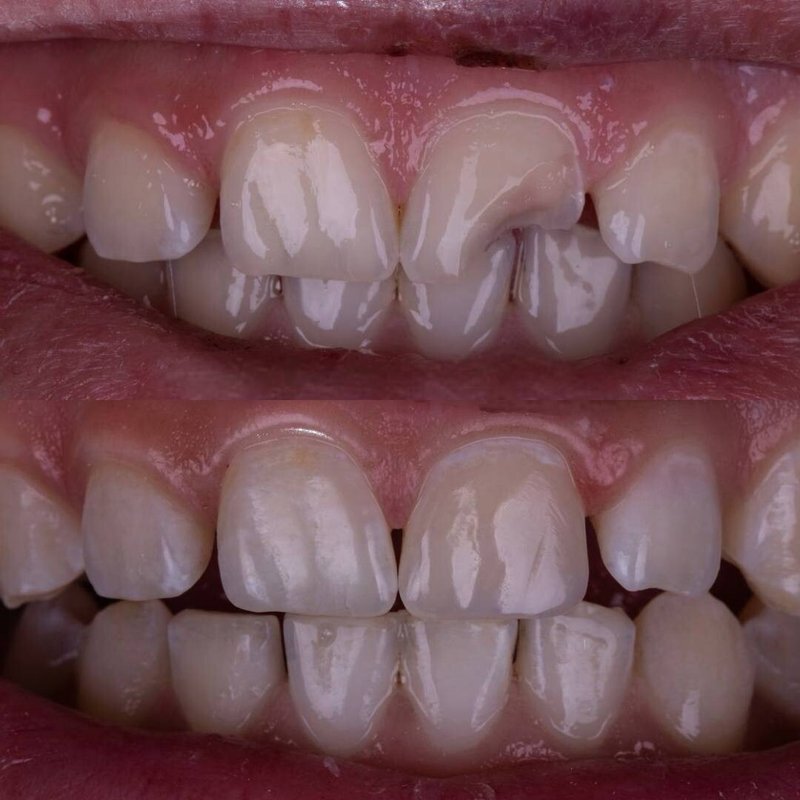

Фотогалерея